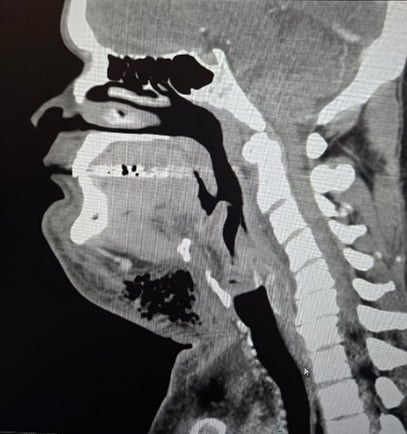

(Left: Figure 1 | Right: Figure 2)

CT soft tissue neck revealed extensive soft tissue swelling with gas formation in the left facial and cervical regions concerning for necrotizing fasciitis, along with narrowing of the hypopharyngeal and laryngeal airway.